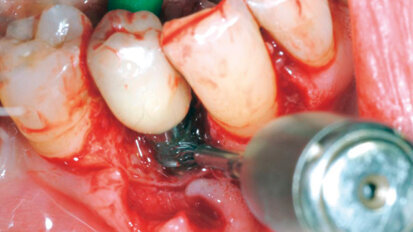

Procedure mininvasive d’aumento e preservazione alveolare (open barrier membrane technique)

Le membrane convenzionali in PTFE espanso (ePTFE) sono state ampiamente usate per la rigenerazione guidata (GBR) e sono divenute uno standard negli anni ...